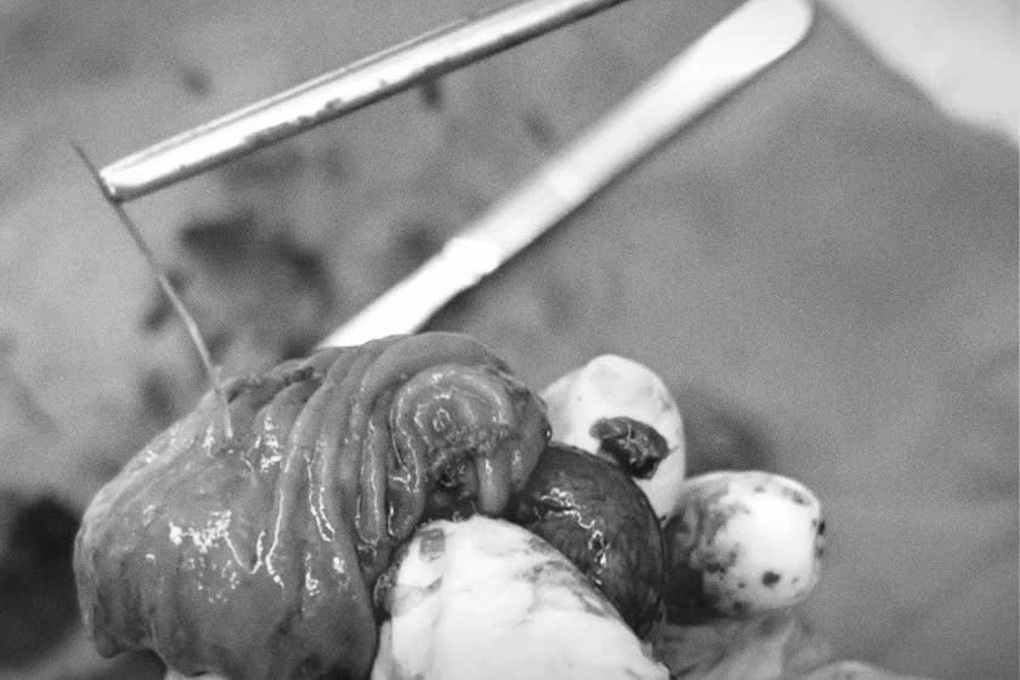

Xương cá đâm thủng ruột non của bệnh nhân (Ảnh: Bệnh viện cung cấp).

Một ổ áp xe tại đoạn ruột non vị trí cách góc hồi manh tràng khoảng 1m, nguyên nhân là mảnh xương cá dài 4cm đâm thủng ruột non.